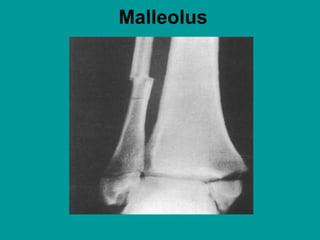

Malleolus

Malleolus.

Fractures involving the malleolus are a

much more common type of ankle

fracture. They can involve the lateral or

medial malleolus, or both, and they usually

result from an external rotation injury to

the ankle. Ligament damage is typical,

generally of the deltoid ligament and of the

anterior and posterior tibiofibular

ligaments. Patients feel immediate pain

and have difficulty walking or cannot walk.

Moderate-to-severe swelling and bony

tenderness exist over the fracture site(s),

with or without a visible deformity.